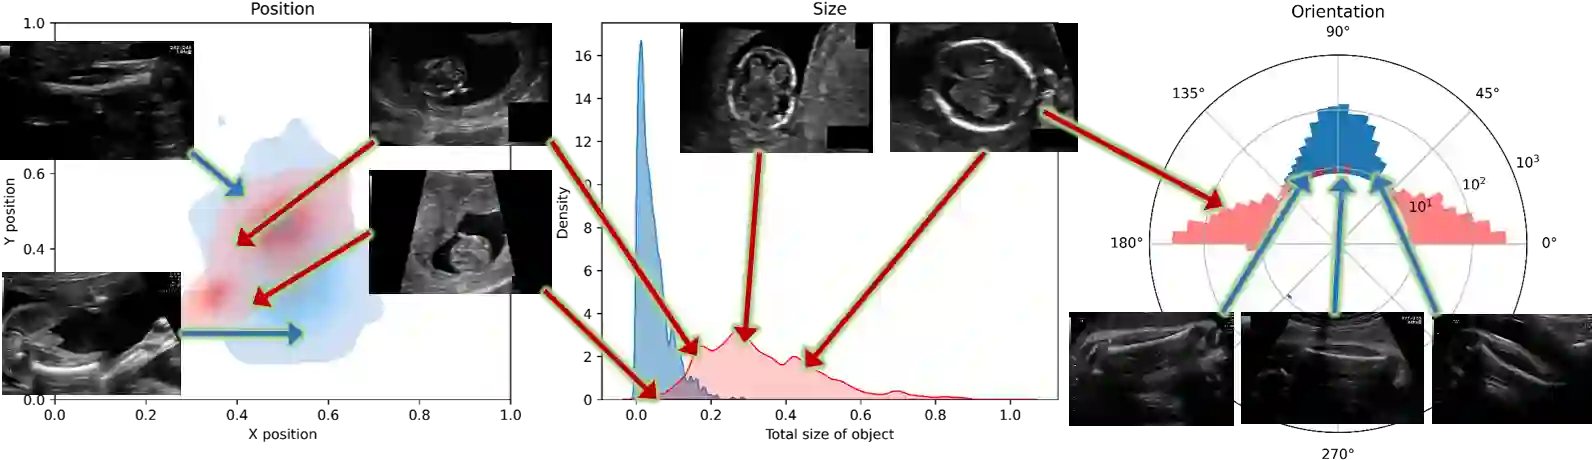

Fetal growth assessment from ultrasound is based on a few biometric measurements that are performed manually and assessed relative to the expected gestational age. Reliable biometry estimation depends on the precise detection of landmarks in standard ultrasound planes. Manual annotation can be time-consuming and operator dependent task, and may results in high measurements variability. Existing methods for automatic fetal biometry rely on initial automatic fetal structure segmentation followed by geometric landmark detection. However, segmentation annotations are time-consuming and may be inaccurate, and landmark detection requires developing measurement-specific geometric methods. This paper describes BiometryNet, an end-to-end landmark regression framework for fetal biometry estimation that overcomes these limitations. It includes a novel Dynamic Orientation Determination (DOD) method for enforcing measurement-specific orientation consistency during network training. DOD reduces variabilities in network training, increases landmark localization accuracy, thus yields accurate and robust biometric measurements. To validate our method, we assembled a dataset of 3,398 ultrasound images from 1,829 subjects acquired in three clinical sites with seven different ultrasound devices. Comparison and cross-validation of three different biometric measurements on two independent datasets shows that BiometryNet is robust and yields accurate measurements whose errors are lower than the clinically permissible errors, outperforming other existing automated biometry estimation methods. Code is available at https://github.com/netanellavisdris/fetalbiometry.